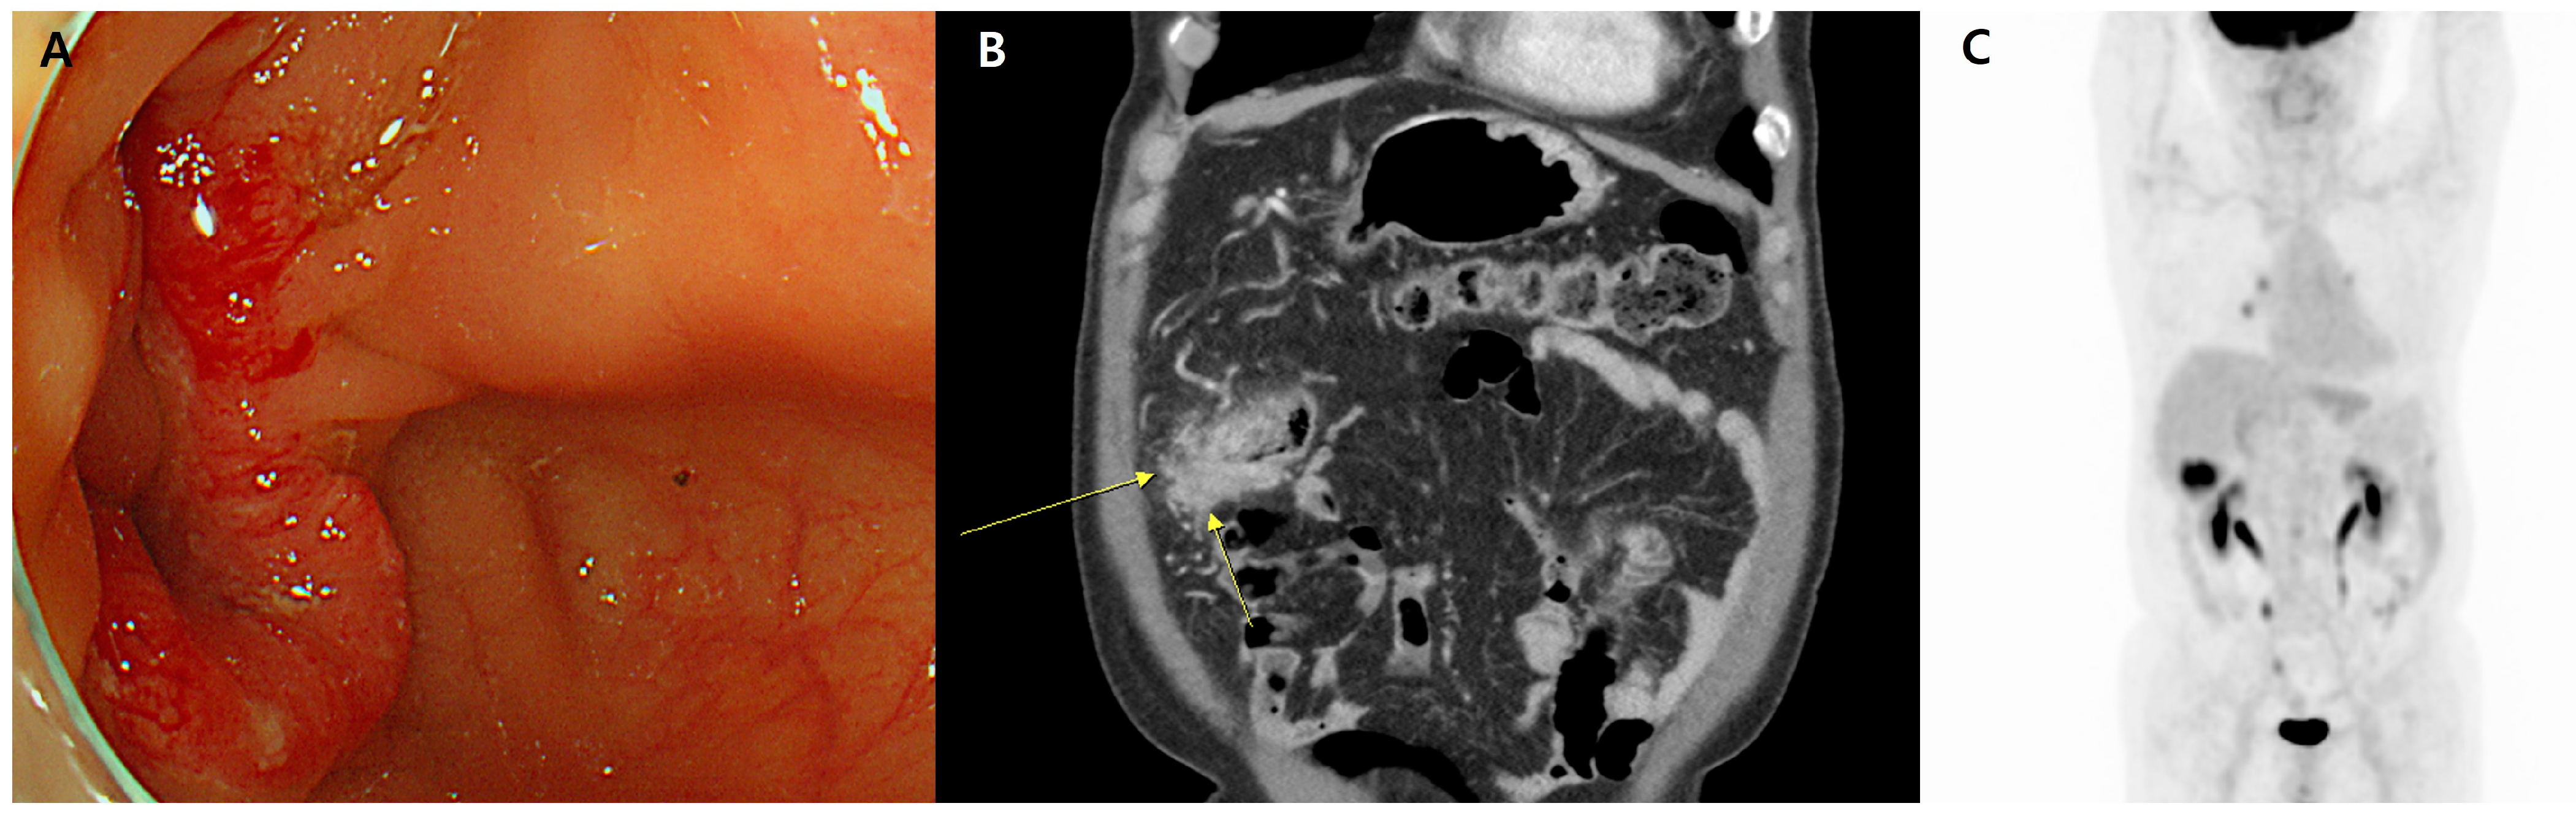

Coexistence of Colorectal Cancer and Immunoglobulin G4-Related Disease in the Same Lesion: A Rare Case with Molecular Classification

Abstract